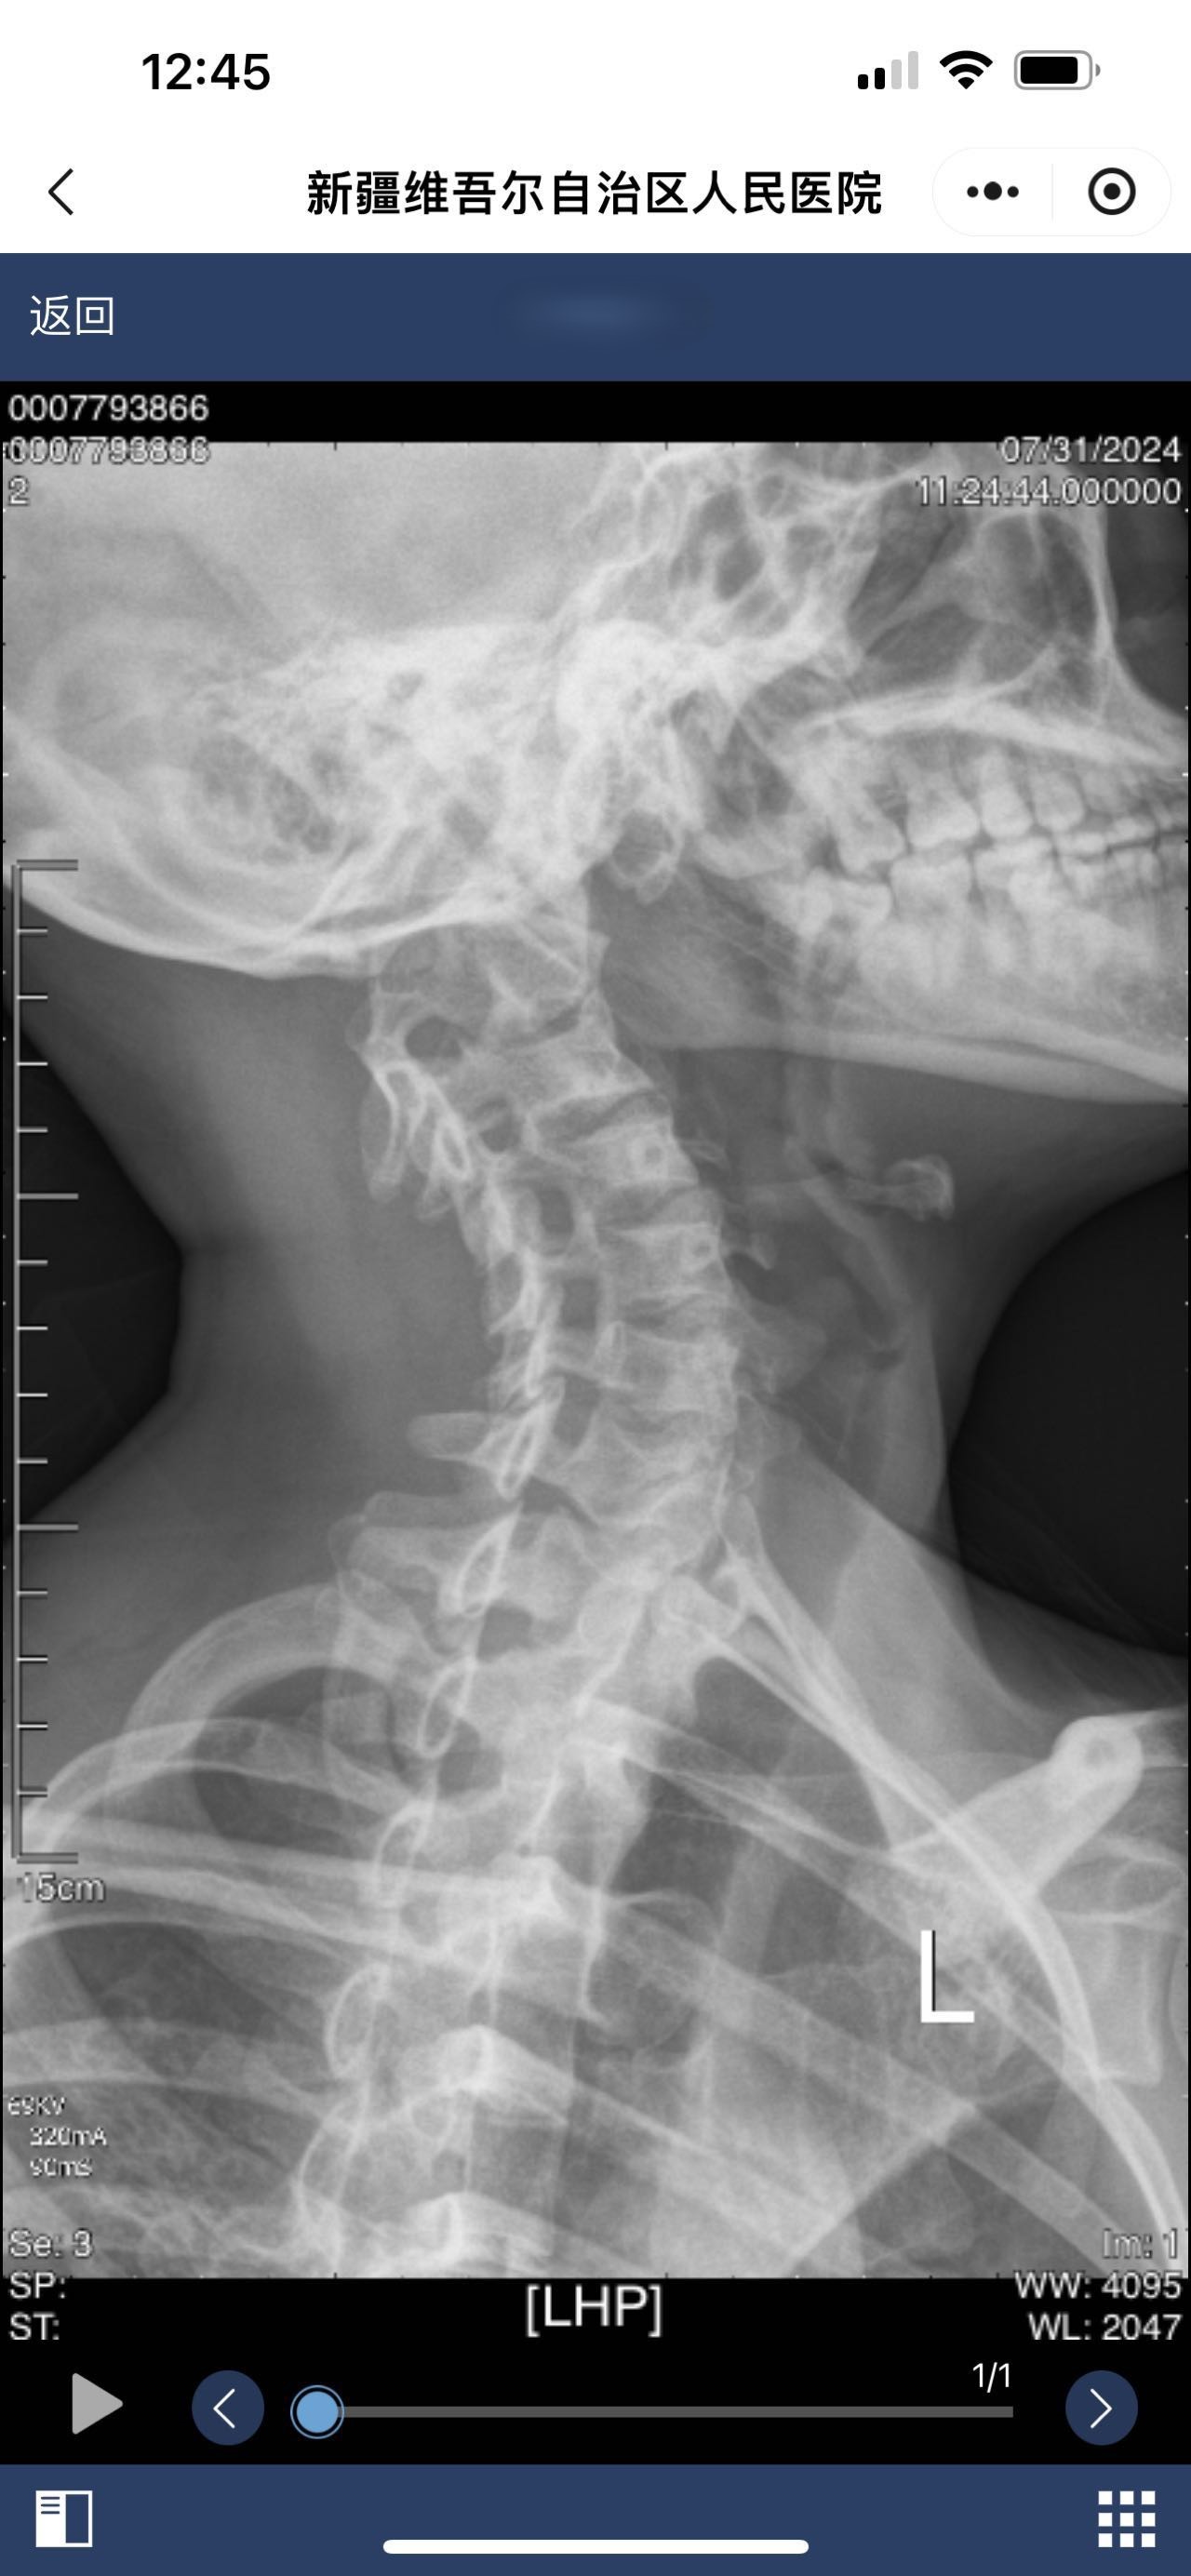

• 诊断日期:2024.07.31

• 诊断:颅底凹陷

• 影像: